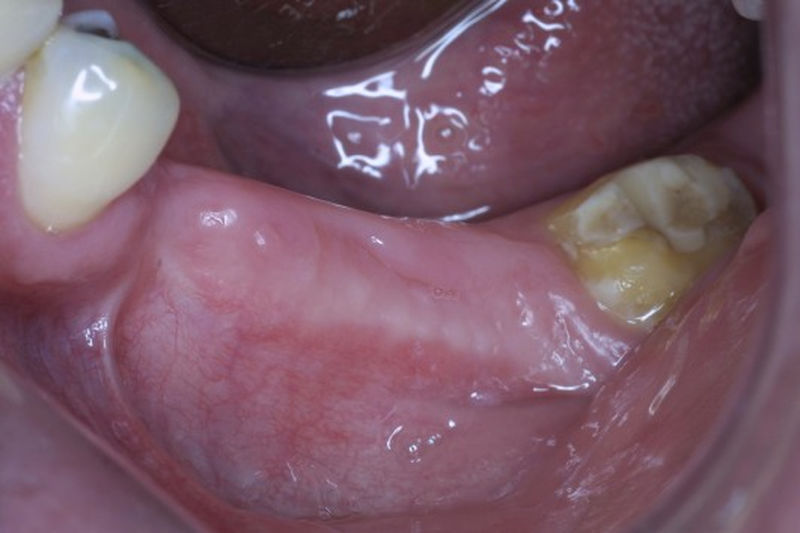

Proceso fundamental y exhaustivo que realiza el odontólogo para identificar la condición de la cavidad oral e identificar tanto zonas que esten sanas como aquellas que no lo son y buscar la causa de cualquier enfermedad o anomalía en la cavidad oral. No se limita a buscar caries, sino que ofrece una evaluación integral que sirve de base para diseñar un plan de tratamiento adecuado, efectivo y personalizado.

Las prótesis dentales son aparatos o dispositivos que se utilizan para reemplazar los dientes ausentes y las estructuras orales relacionadas.

Los implantes dentales son pequeños tornillos de titanio u otro material biocompatible que se insertan en el hueso maxilar o mandibular para sustituir la raíz de un diente perdido. Actuando como un soporte sólido sobre el cual el dentista puede colocar un diente artificial (corona), un puente o una prótesis completa.

Son estructuras de titanio las cuales se colocan en el hueso y se utilizan para soportar coronas, prótesis fijas, removibles y totales. La colocación de los implantes se hacen previo análisis tomográfico.